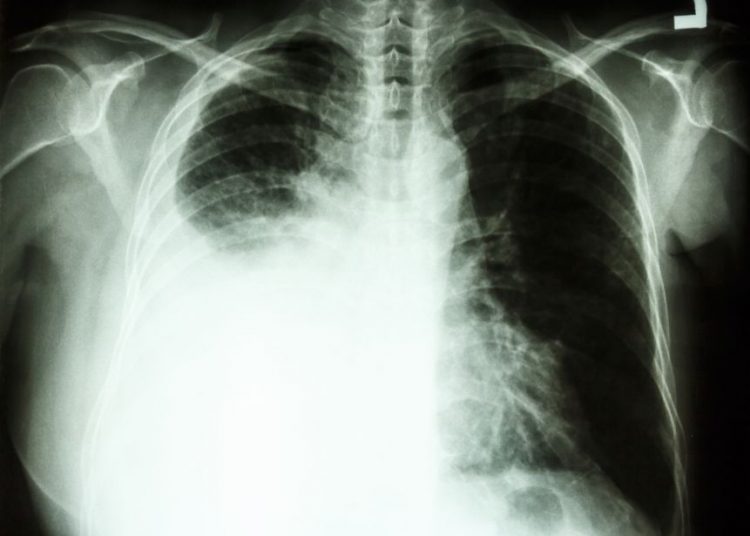

Types of lung cancer

Cancer that starts in the lungs is called non-small cell lung cancer (NSCLC). The most common types are adenocarcinoma, squamous cell carcinoma and large-cell carcinoma.

These cancers start in the cells that line the airways of the lungs.